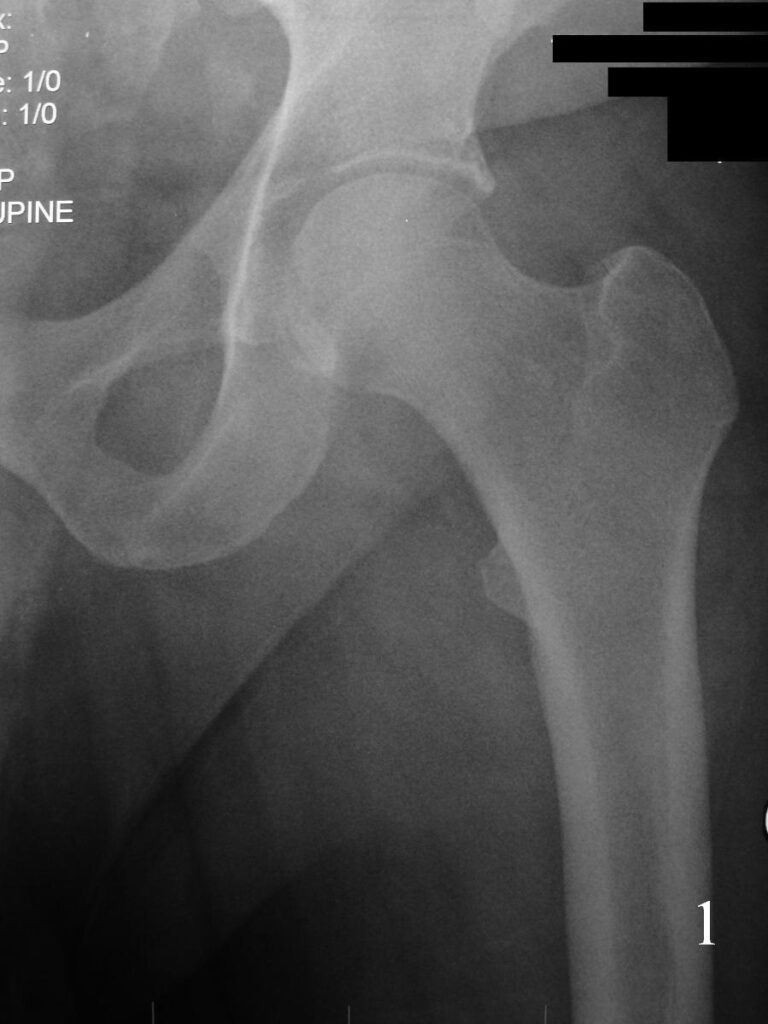

X-ray (Fig. 1-2)

Fig. 1

Fig. 2

Fig 1-2. AP X-ray and lat (Fig. 2) of left hip shows a nonspecific soft tissue mass.